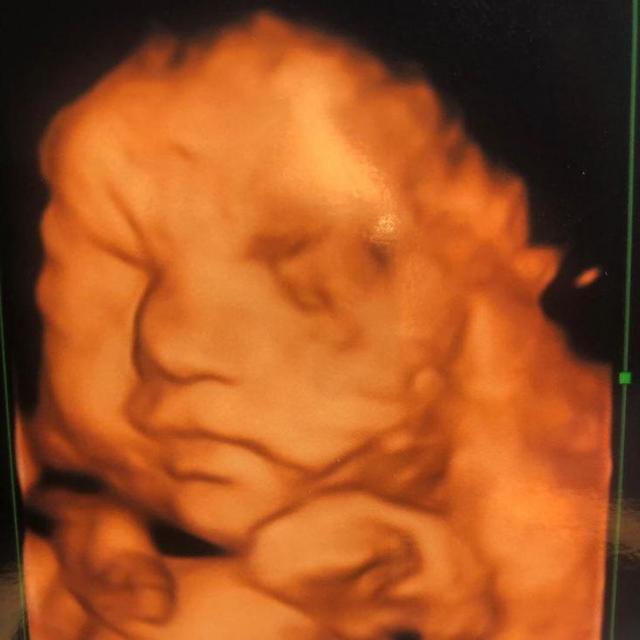

露娜出生前,她的父母都没有料到宝贝女儿会是这样,因为各种产检指标都显示正常。

光敏印章怎么加油,原子公章和光敏章的区别(萌娃因“蝙蝠侠”胎记遭网暴)

超声波也完全看不出来。